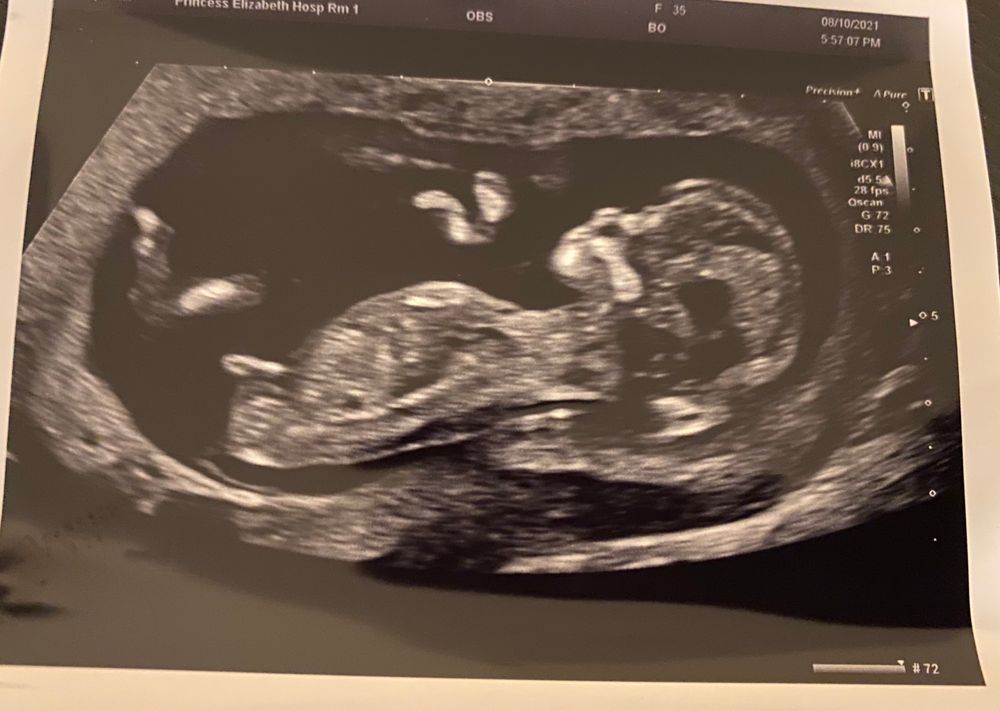

УЗИ 13 недель

УЗИ, КТГ, доплерВот и состоялось первое, долгожданное узи. Можно выдохнуть: все параметры соответствуют нормам. А вот пол не сказали( Девочки, есть ли те кто могут предположить. Буду благодарна. Всем легкой беременности и здоровых малышей